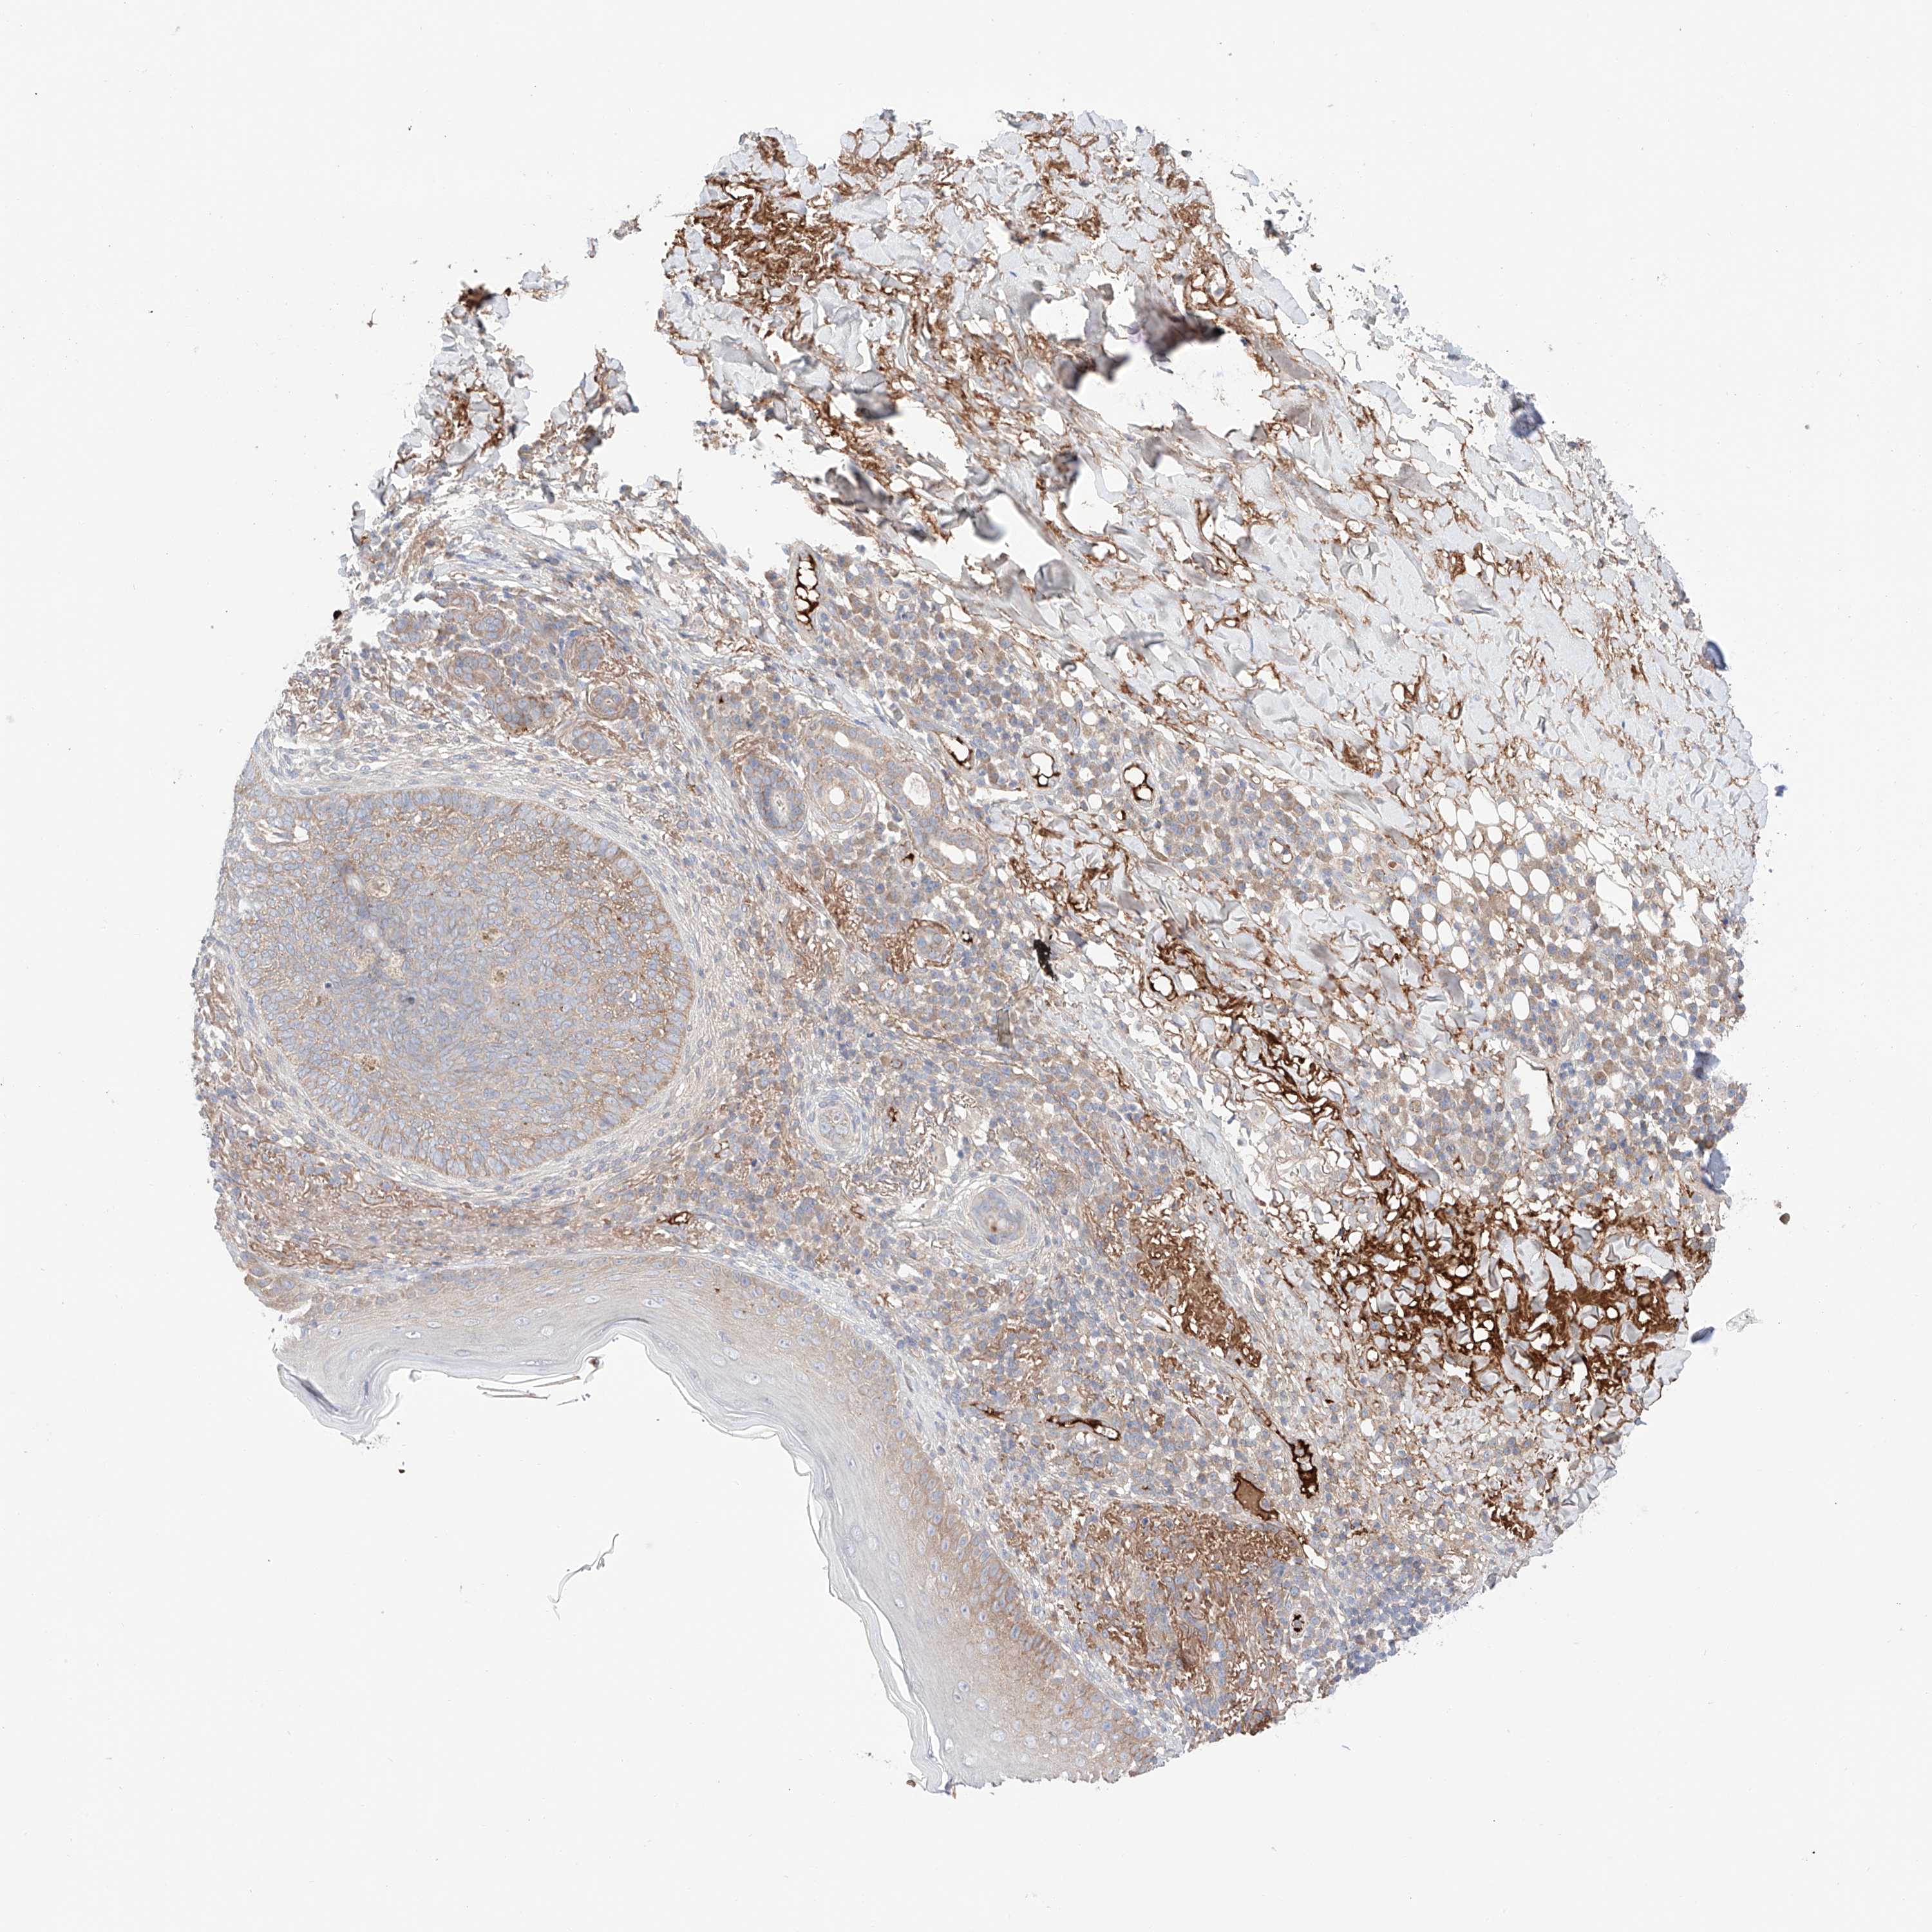

SKIN CANCER - Protein expressioni

A mouse-over function shows sample information and annotation data. Click on an image to view it in a full screen mode. Samples can be filtered based on level of antibody staining by selecting one or several of the following categories: high, medium, low and not detected. The assay and annotation is described here.

Antibody stainingi

Antibody staining in the annotated cell types in the current human tissue is reported as not detected, low, medium, or high, based on conventional immunohistochemistry profiling in selected tissues. This score is based on the combination of the staining intensity and fraction of stained cells.

Each image is clickable and will lead to virtual microscopy that enables deeper exploration of all samples and also displays staining intensity scores, fraction scores and subcellular localization as well as patient and tissue information for each sample.

Antibody HPA030646

Staining

High

Medium

Low

Not detected

Intensity

Strong

Moderate

Weak

Negative

Quantity

>75%

75%-25%

<25%

None

Location

Nuclear

Cytoplasmic/membranous

Cytoplasmic/membranous,nuclear

Squamous cell carcinoma, metastatic, NOS